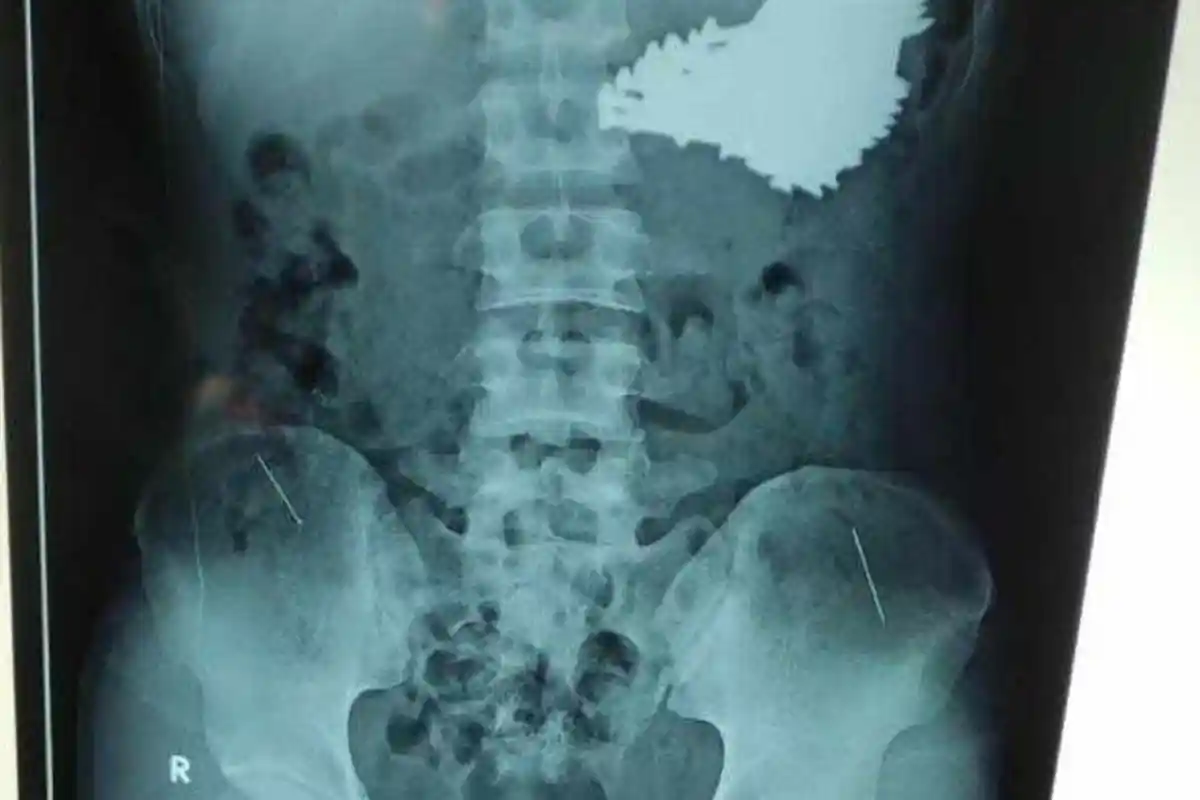

Kondisi SH , pria ODGJ usia 22 tahun ini terkuak dari hasil rontgen yang menunjukkan banyak paku berukuran besar di dalam lambungnya.

Dari hasil rontgen, terdapat puluhan paku yang bersarang di dalam lambung.

Di lambung pria tersebut ditemukan 70 paku.

Kondisi SH pun terkuak dari hasil rontgen yang menunjukkan banyak paku berukuran besar di dalam lambungnya.

Dari dalam perutnya berhasil dikeluarkan 70 paku yang sudah berkarat.